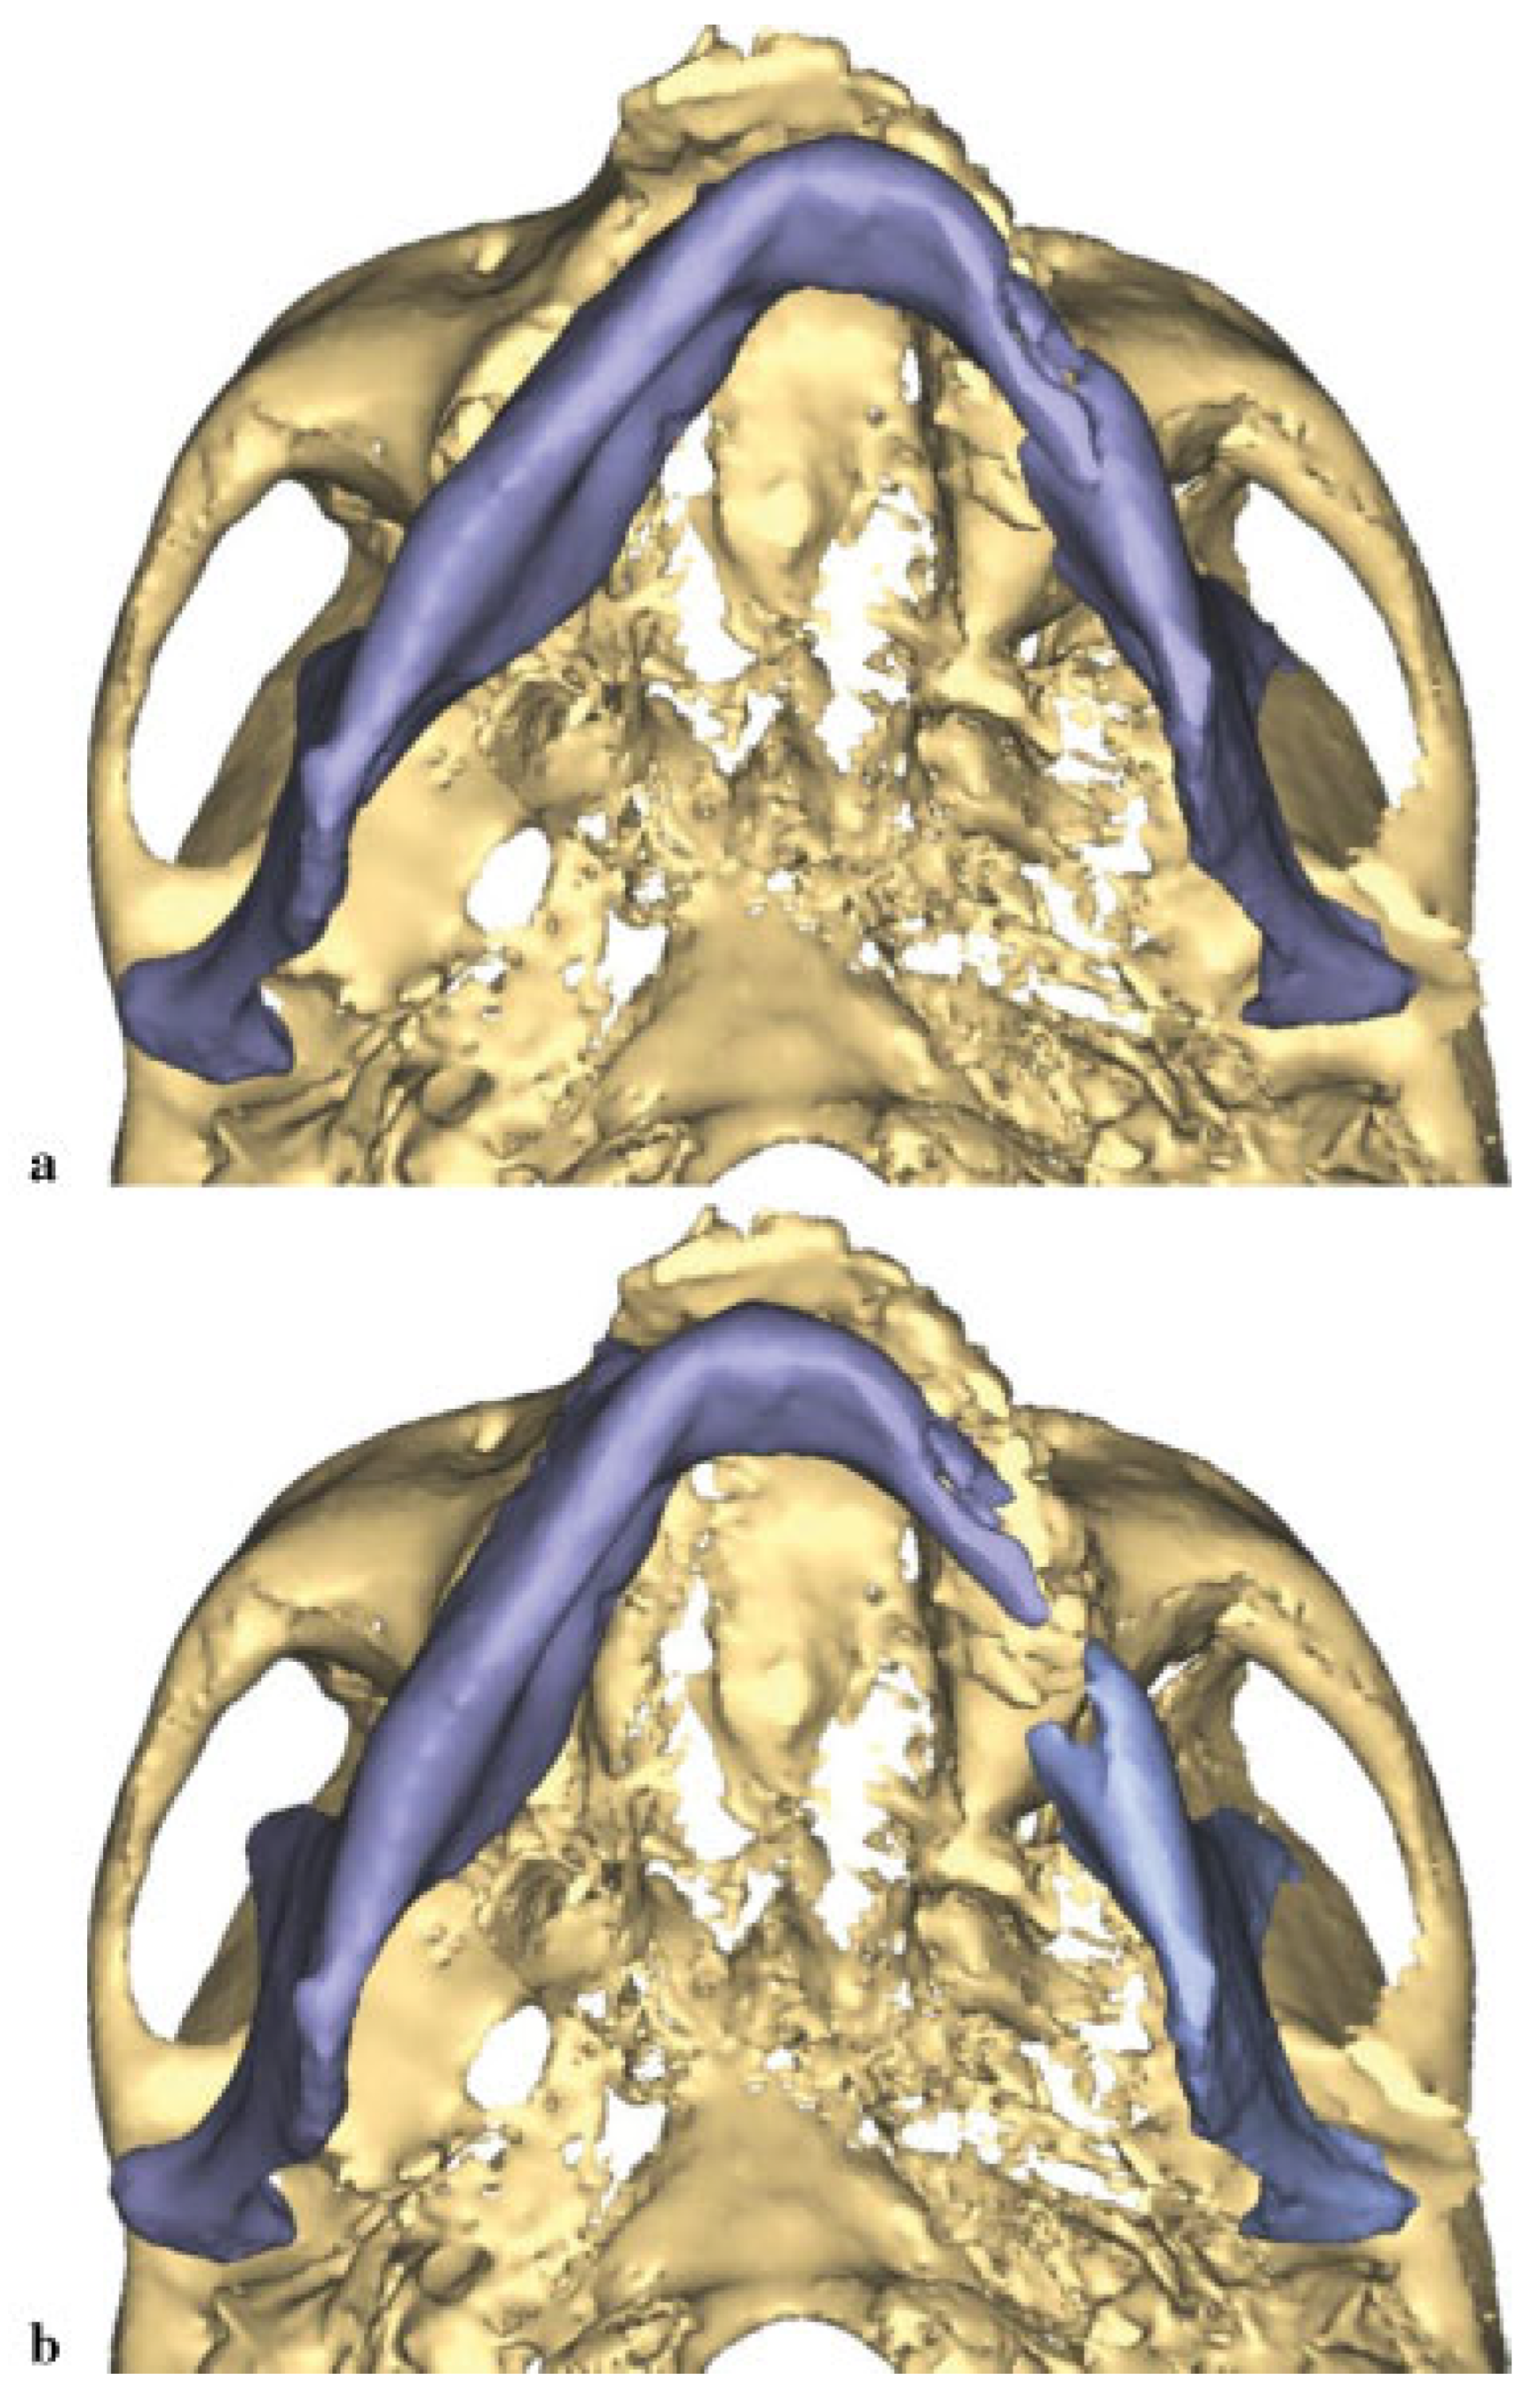

Owing to the significant injury to the anterior and posterior column of the cervical spine, a fusion was performed of C5–T1. Prior to surgery, he was kept in a cervical spine collar. To minimize the time in the operating room (OR) and manipulation of the displaced, atrophic mandible, his initial CT scans were used to fabricate a model to facilitate the correction of the complex mandible fracture. Turnaround time was 5 days. Using three-dimensional (3D) software for VSP (Materialize, Plymouth, MI), the midline of the larger segment of the mandible was aligned with the midline of the maxilla (Figure 2a,b). A mirror image was created using the opposing uninjured mandibular body (Figure 3a,b). A stereo-lithographic model was fabricated facilitating the preoperative bending of a 2.5-mm reconstruction plate, based on the virtually planned model (Figure 4). The plate was contoured to the model the evening before surgery.

Figure 3. (a) A mirror image as seen from frontal. (b) Mirror image as seen from submental vertex.